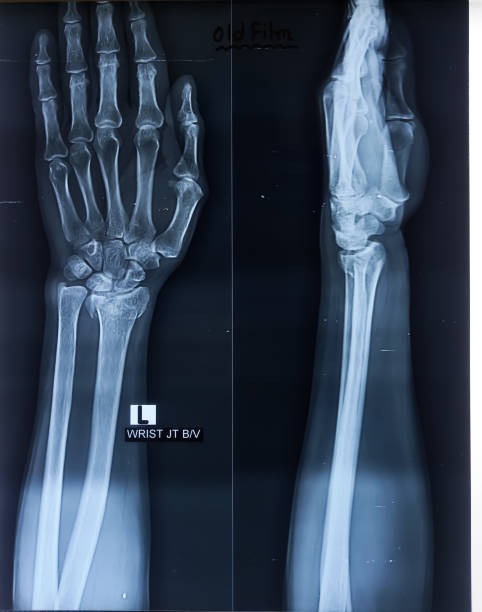

해부학적 이상은 척골충돌증후군의 주요 원인 중 하나로, 팔꿈치와 손목 사이의 뼈 구조나 관절 배열에 선천적 혹은 후천적 변형이 있을 때 발생할 수 있습니다. 예를 들어, 척골이 정상보다 길거나 뼈의 돌출부가 비정상적으로 발달하면 손목과 척골 사이의 공간이 좁아져 충돌이 발생하기 쉽습니다. 이런 구조적 이상은 일상적인 움직임에서도 반복적으로 뼈와 인대, 힘줄 사이에 마찰을 일으켜 염증과 통증을 유발합니다. 해부학적 이상은 개인마다 다르게 나타나며, 증상이 심하면 기능 저하와 만성 통증으로 이어질 수 있습니다. 정확한 진단을 위해 X-ray, MRI 등의 영상 검사가 필요하며, 치료는 보존적 방법부터 수술적 교정까지 다양하게 적용됩니다. 조기에 이상을 발견하고 적절한 관리와 운동으로 관절의 움직임을 개선하는 것이 중요합니다.